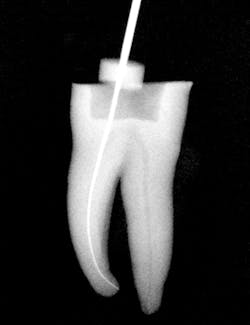

Figure 1: Radiograph of extracted tooth to demonstrate preoperative canals.

After preparing straight-line access to the canal orifice (figure 1), explore the canal using small-sized instruments. I typically use a size 08 SafeSider by hand with the help of an apex locator to determine working length. I then use the SafeSiders in sizes 10, 15, and 20 to verify patency and confirm a smooth, reproducible glide path (figure 2). I always irrigate and enlarge the glide path to a minimum 20/02 preparation.